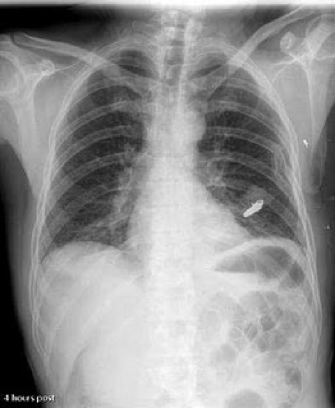

•Chest:

–Lung (air), Ribs (bone), heart (muscle)

–High subject contrast: mostly black and white, with some grays in between